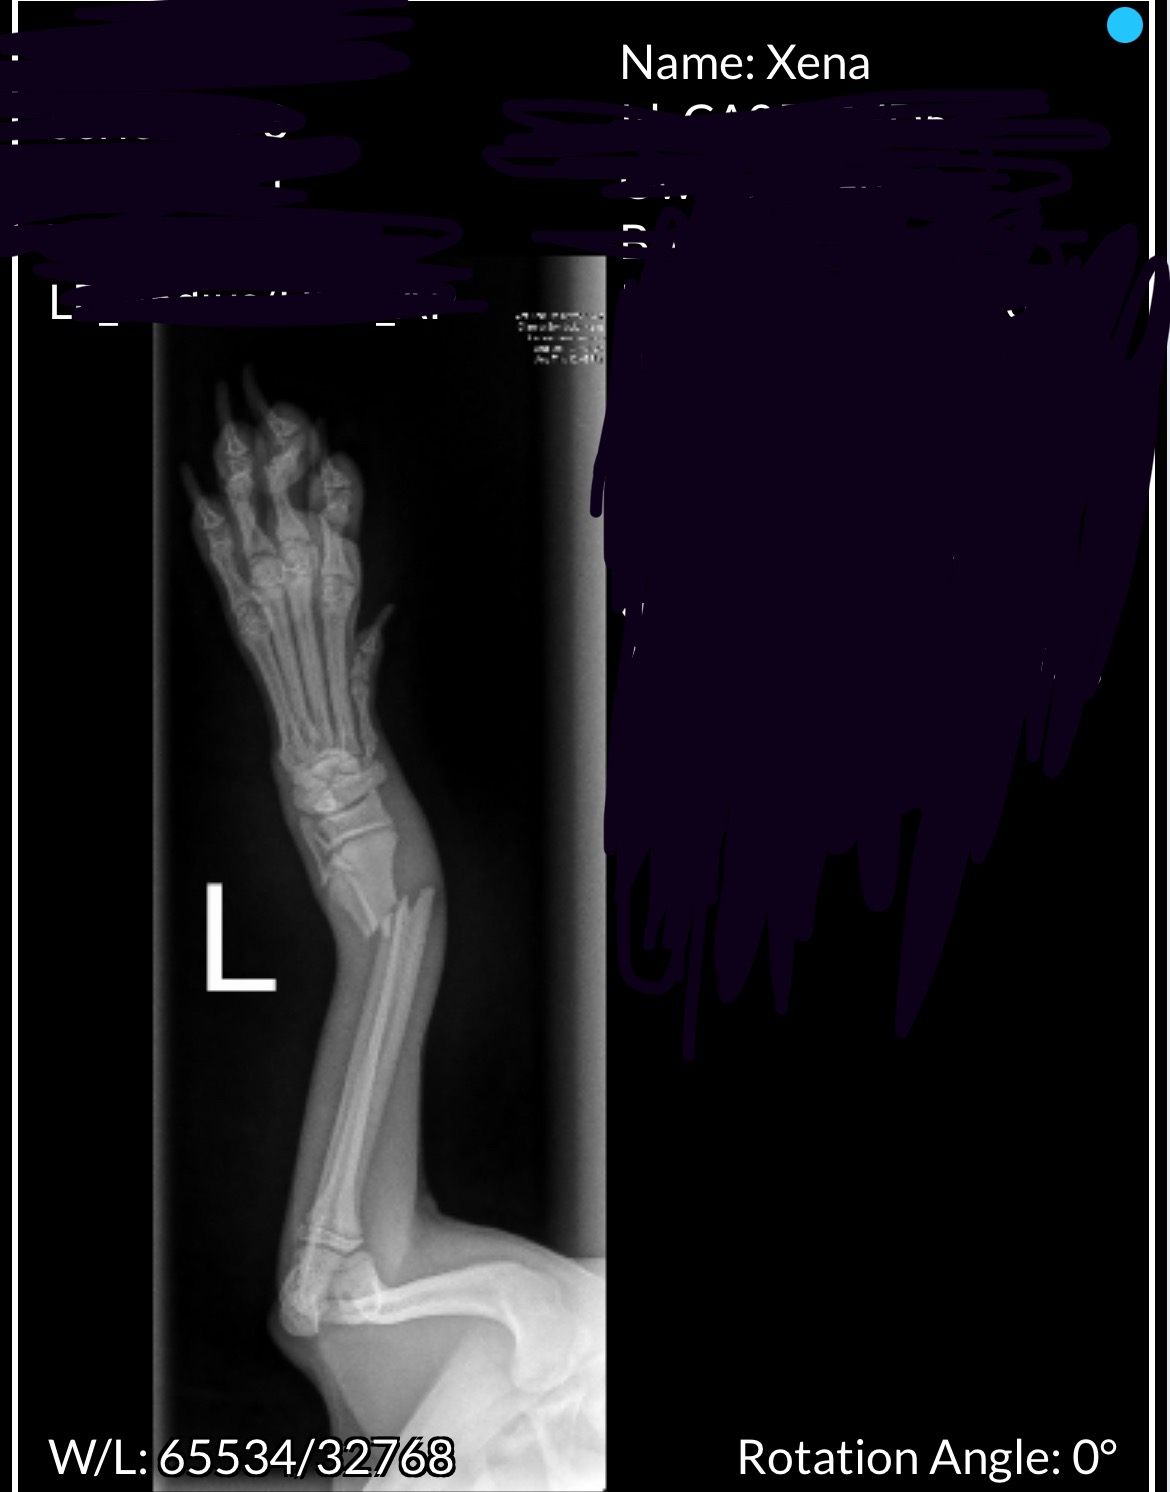

On December 7th, 2025, Xena was playing on the couch with my cats when she slipped, lost her footing, and fell. For most dogs, a fall like this might be something they could shake off — but Xena is extremely tiny for her age, weighing only 0.9 kg. For a girl her size, it was a much bigger impact than it would be for most puppies.

Even through the pain, Xena has been so strong and has kept her sweet, happy-puppy spirit. Unfortunately, she now needs surgery to place screws and stabilize her leg so her bones can heal properly. This will give her the best chance at living a healthy, comfortable, and normal life.